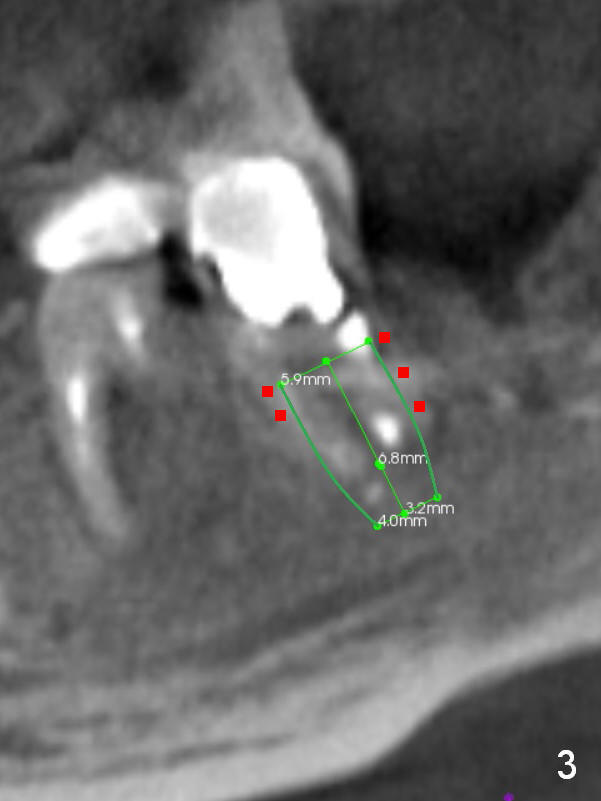

A 39-year-old man (ZC) fractures the lingual portion of the tooth #31 while eating peanut during Christmas (Fig.1 green arrows), a few months finishing #28,29 implant crowns. It fractures between the large amalgam (Fig.3 A) and the lingual portion of the tooth (L). It should be subgingival and nonsalvageable. Prepare crown prep or immediate implant. If the latter is indicated, the socket will be treated with 2% Xylocaine/1:50,000 Epinephrine. The distance between the apex of the socket and the Inferior Alveolar Canal is >5 mm (Fig.2,4). If osteotomy is controlled 3 mm beyond the apex of the socket, it is safe (Fig.3,5). A 5.9x10 or 12 mm implant should be able to engage to the buccal and lingual walls for additional stability (Fig.5), while there will be mesial and distal gaps to be filled with bone graft (Fig.3 red dots).